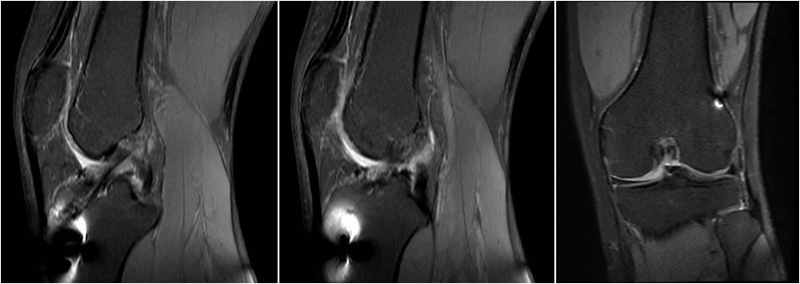

MRI检查评估ACL-R术后——韧带连续性信号好、方向好、愈合快,没有Cyclops综合征。

典型病例,张X,男,18岁,因扭伤致左膝关节疼痛伴活动受限1月余入院。

诊断:1.左膝前交叉韧带损伤;2.左膝外侧半月板损伤合并囊肿。

手术方案:左膝关节镜下清理、滑膜切除、外侧半月板部分切除成形、前交叉韧带重建术。

术前MRI

术后MRI